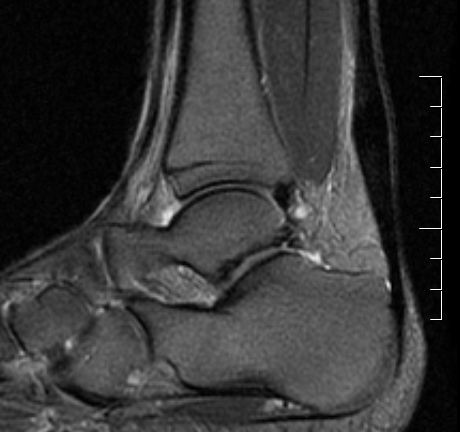

MRI

Tendon thickening

Thickening of the tendon with some intra-substance degeneration / partial tearing